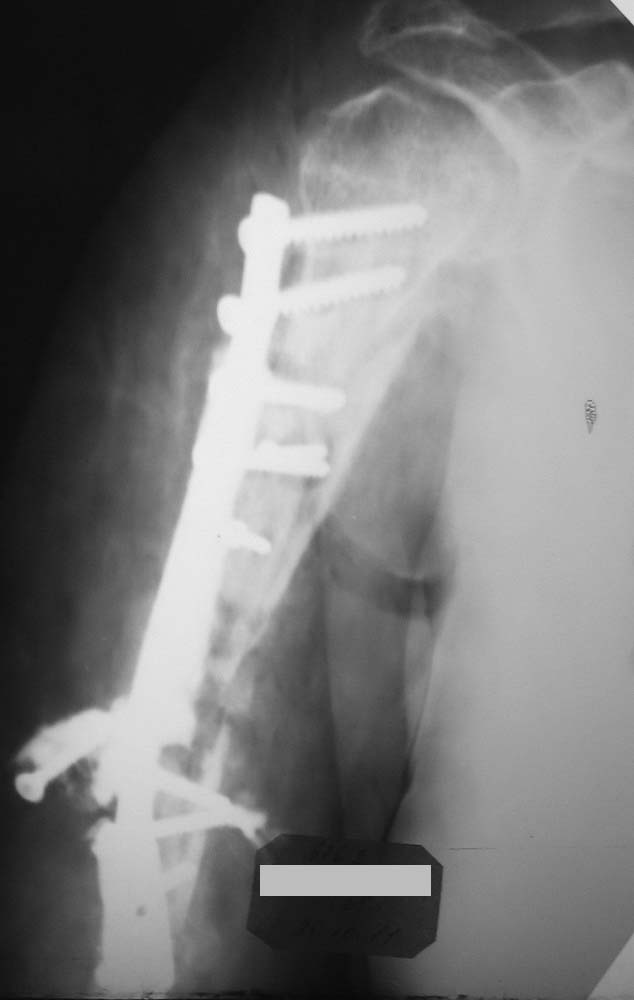

Штифтами для интрамедуллярного синтеза не было, поэтому синтезировали тем, что было (пластина на 11 отверстий).

Снимки, к сожалению, оставляют желать лучшего.

Но то, что я вижу нельзя отнести к стабильному остеосинтезу.Раз уж Вы открылись "по полной" то важно хорошо репонировать отломки и зафиксировать винтами через оба кортикала. Возможно были интраоперационные проблемы,которые как-то помешали это сделать.Понять и осмыслить свои ошибки - это путь к их предотвращению в дальнейшем, ведь от этого никто не застрахован :)

Виктор! Начну с вопроса - что остановило первично заштифтовать, а не идти открыто? При такой установке пластины, Вы сразу дали шанс сломаться всему повторно. Если оставлять в аппарате, то срастаться будет лет так надцать (дефект около 10 см). Сохраните длину конечности и синтезируйте штифтом, ранняя нагрузка и штифт будет выполнять у Вас роль внутреннего эндопротеза и пусть срастается, главное будет рабочая рука, а не красивый рентген снимок.

В приложении один из возможных вариантов решения проблемы на плече.